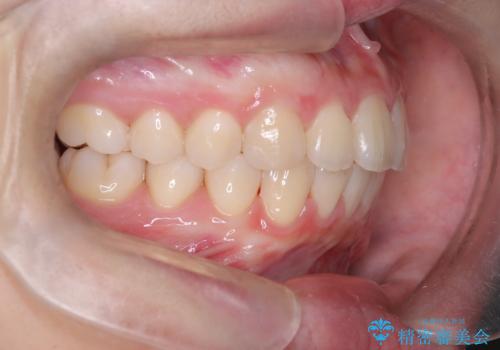

上と下の前歯がずれているため、抜歯を行い前歯の真ん中を合わせる治療計画を立ててワイヤー矯正にて治療を行いました。

途中、矯正用のアンカースクリューを使うことで、最終的にきれいに前歯の真ん中を合わせることができました。

2年という矯正期間でしたが、かみ合わせも良くなりを患者様には満足していただくことができました。